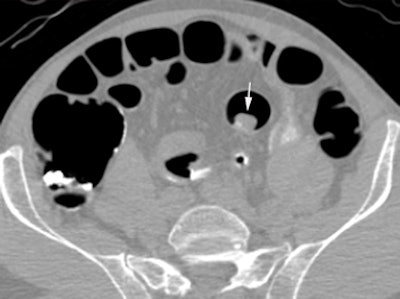

| Above, supine virtual colonoscopy image shows a 20-mm adenoma (arrow) in the sigmoid colon. Below, fused PET/CT in the same patient shows an area of intense F-18 FDG uptake corresponding to the 20-mm adenoma. A small amount of misregistration is present. Arrowhead points to ureteric activity. All images courtesy of Dr. Stuart Taylor. |

Of the 14 polyps that were 6 mm or larger in diameter, 12 (86%, 95% CI: 67%-100%) were avid for F-18 FDG, including all of the lesions 10 mm or larger (mean standardized uptake value [SUV], 10.1), Taylor and his team wrote. Moreover, the group found no significant difference in mean SUV for adenomas with (mean, 12.7) and without (mean, 7.4) high-grade dysplasia (p = 0.10).

A single 6-mm polyp missed on CTC was not F-18 FDG-avid, nor was there uptake in any polyp 5 mm or smaller.

CTC's sensitivity for polyps 6 mm or larger of 92.9% (95% CI: 79.4%-100%) did not improve with the addition of PET. However, the combined exam did improve the per-patient positive predictive value for a polyp 10 mm or larger from 73% (95% CI: 39%-92%)to 100% (95% CI: 60%-100%).